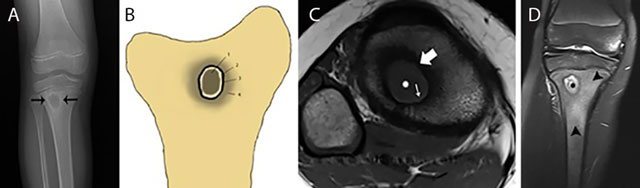

Figure 10

Typical Brodie abscess in subacute osteomyelitis of the tibia. Plain radiograph (a) Schematic drawing (b) Axial T1–WI (c) and coronal Fat–Sat T2–WI (d) Plain radiograph (a) shows a focal area of metaphyseal osteolysis with a peripheral rim of reactive sclerosis (black arrows). (b) shows a the different layers of Brodie abscess on T1–WI with a the pathognomonic penumbra sign on axial T1–WI (c) and a pus-filled collection on coronal Fat–Sat T2–WI (d). Central pus of intermediate to low SI on T1–WI (white asterisks on c) and high SI on T2–WI (black asterisks on d). Internal abscess wall consisting of granulation tissue of high SI on T1–WI (penumbra sign) (white small arrow on c) and intermediate SI on T2–WI. External ring of reactional sclerosis of low SI on both T1–WI (white large arrow on c) and T2–WI. Peripheral bone marrow edema of intermediate to low SI on T1–WI and high SI on T2–WI (black arrowheads on d).